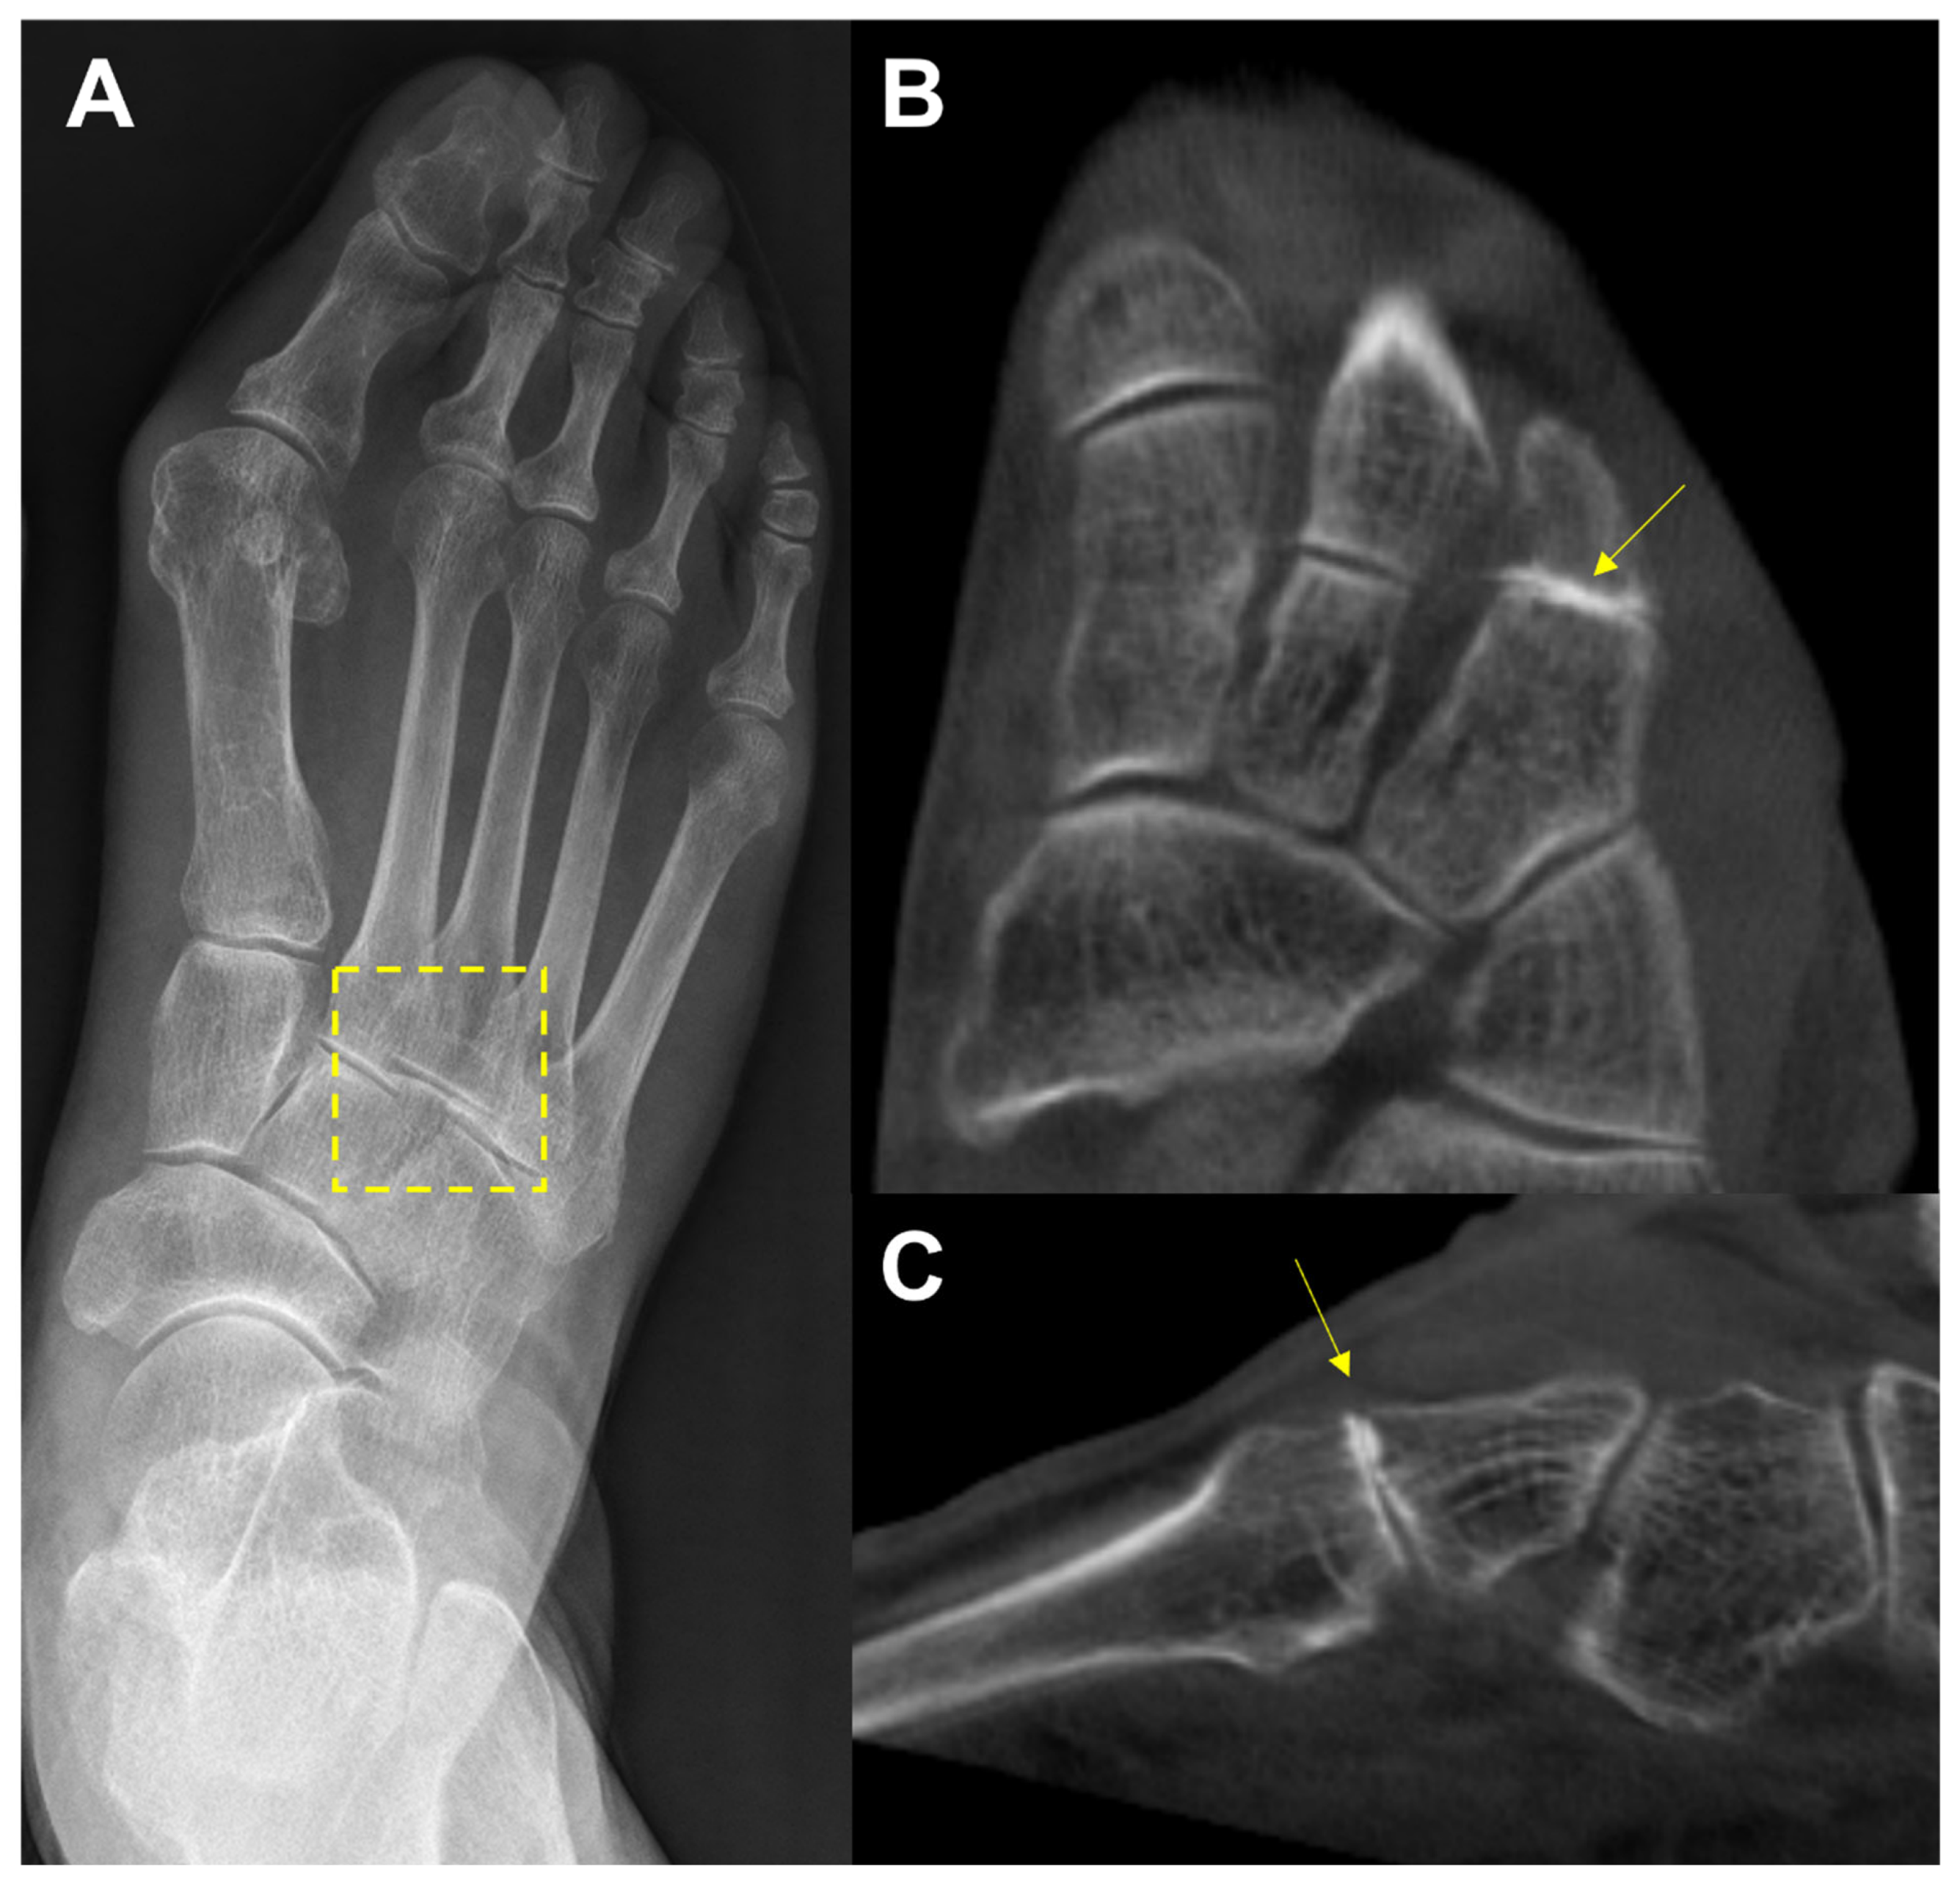

Figure 6. In the plain radiograph, osteoarthritis of the third tarsometatarsal (TMT) joint is not clearly visible (A); however, weight-bearing computed tomography (WBCT) reveals distinctive joint space narrowing and sclerotic changes (B, C).

In the midfoot, precise identification of associated articulations and osseous borders in conventional weightbearing radiographs may not be handy because it can be affected by overlapping of adjacent bones viewed two-dimensionally [29]. (Figure 6) For this reason, WBCT could be an alternative as it enables clear joint space visualization and enhanced bony landmark identification under physiological weightbearing condition. Steadman et al compared weightbearing radiograph and WBCT with regards to diagnostic accuracy in midfoot osteoarthritis [30]. They found that weightbearing radiograph demonstrated 61.5 to 72.5 % sensitivity and 87.9 to 96.1 % specificity in identifying midfoot osteoarthritis. It also showed less accurate localization of degenerative changes and a greater tendency to underestimate disease severity compared to WBCT. These findings indicate that WBCT would be a better diagnostic option in midfoot osteoarthritis as it provides earlier and more reliable diagnosis.

Instead of conventional axial measurement of the Lisfranc joint, some novel WBCT parameters have been developed and introduced to be used in the clinical setting. Sripanich evaluated 96 cadaveric specimen and designed a WBCT protocol to enhance the reliability of Lisfranc joint measurement [27]. They found that measuring the distance between medial cuneiform and second metatarsal with coronal WBCT imaging would be a reproducible way to localize the interosseous Lisfranc ligament injury. Similarly, Bhimani et al evaluated the Lisfranc joint complex using one dimensional (1D), two dimensional (2D), and 3D measurements on WBCT scans among operatively confirmed Lisfranc instability (Figure 5) [28]. They concluded that coronal 3D volumetric measurement had higher sensitivity and specificity than 2D and 1D measurements, because the second metatarsal tends to displace both laterally and superiorly in Lisfranc injury. Despite its inherent limitation to be actively used in acute condition, WBCT may enhance diagnostic accuracy for suspicious Lisfranc injuries with uncertain conventional radiograph findings.